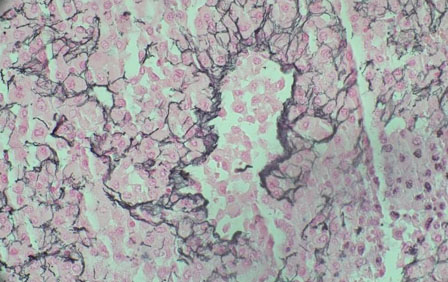

The histological characteristic of OAC is the presence of large polygonal cells with abundant eosinophilic cytoplasm, as a result of mitochondrial accumulation [3]. The diagnostic criteria used for ACC, the Weiss system, overestimates malignant potential in oncocytic tumors, therefore a separate classification system called the Lin–Weiss–Bisceglia (LWB) classification is used for oncocytic tumors [5],[8]. The LWB system divides oncocytic adrenocortical neoplasms (OANs) into benign, borderline, and malignant categories based on three main criteria: a mitotic rate greater than 5 per 50 high-power fields, vascular invasion, and metastasis. Malignancy is diagnosed if any of these criteria are present, while borderline tumors show only minor criteria, such as a tumor size greater than 10 cm, necrosis, or capsular invasion. This classification system has enhanced the ability to differentiate between benign oncocytic adenomas and OACs. In our patient, the resected specimen showed a well-circumscribed tumor weighing 5458 g, and measuring 26.0 × 25.0 × 16.0 cm. The tumor also had extensive hemorrhage and necrosis, along with a central fibrous scar [9]. Microscopically the patient’s tumor matched the classic histological findings for OAC and exhibited a low Ki-67 index of 2% suggesting a low proliferative rate. However, the tumor did exhibit vascular (renal vein) and capsular invasion (Figure 3, Figure 4, Figure 5, Figure 6). Based on the LWB criteria, malignancy was established due to the vascular invasion. Next-generation-sequencing (NGS) showed TP53 pathway alterations. The malignancy had a low tumor mutation burden and was found to be microsatellite stable. These findings are consistent with recent research suggesting a distinct mitochondrial metabolic profile with an oncocytic variant of ACC [4].

Figure 4: Sinus invasion, reticulin stain.